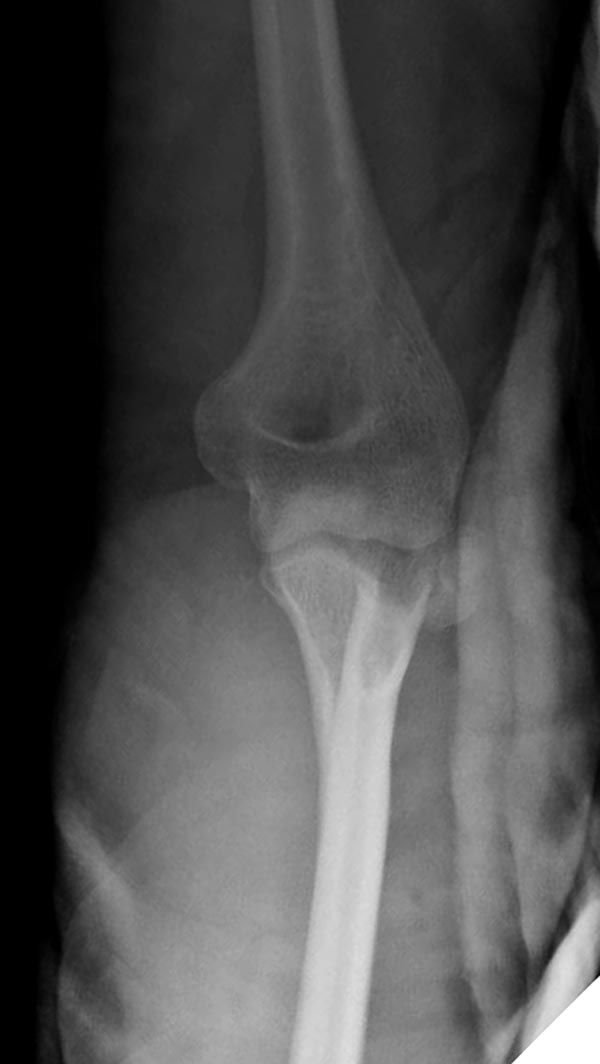

Вместе обычных простых рентгенограм, участились злоупотребления дорогими исследованиями. Хотя многие переломы, даже внутрисуставные, можно увидеть на обычных рентген снимках. Негативный рентген при исследовании локтевого сустава не означает отсутствие перелома. Если имеется “fat pad sign”, характерный симптом для внутрисуставных повреждений, тогда можно ставить диагноз перелом головки луча! Гематома внутрисуставного перелома смещает жировое тело и на боковом снимке проявляется в виде “паруса”.

На переломы головки луча надо обратить внимание, потому что головка луча является важным стабилизатором в локтевом суставе: удерживает от заднего вывиха и от боковых смещений. Изолированный перелом головки луча встречается очень редко и, в основном, в сопровождении с другими повреждениями, вывихом сустава, переломом Monteggia, венечного отростка или повреждением латерального лигамента.

Здесь представлены несколько случаев и как видно больше больных с серьезными повреждениями, чем изолированные..

В первом случае перелом Монтеджи, где доперационно сделано оценка положения головки к остальным элементам под рентгеном. Учитывая правильность взаимотношении произведена фиксация только локтевого отростка, Второй случай, заменена на протез, и третий, кроме фиксации головки - реконструкция capitellum латерального мыщелка.